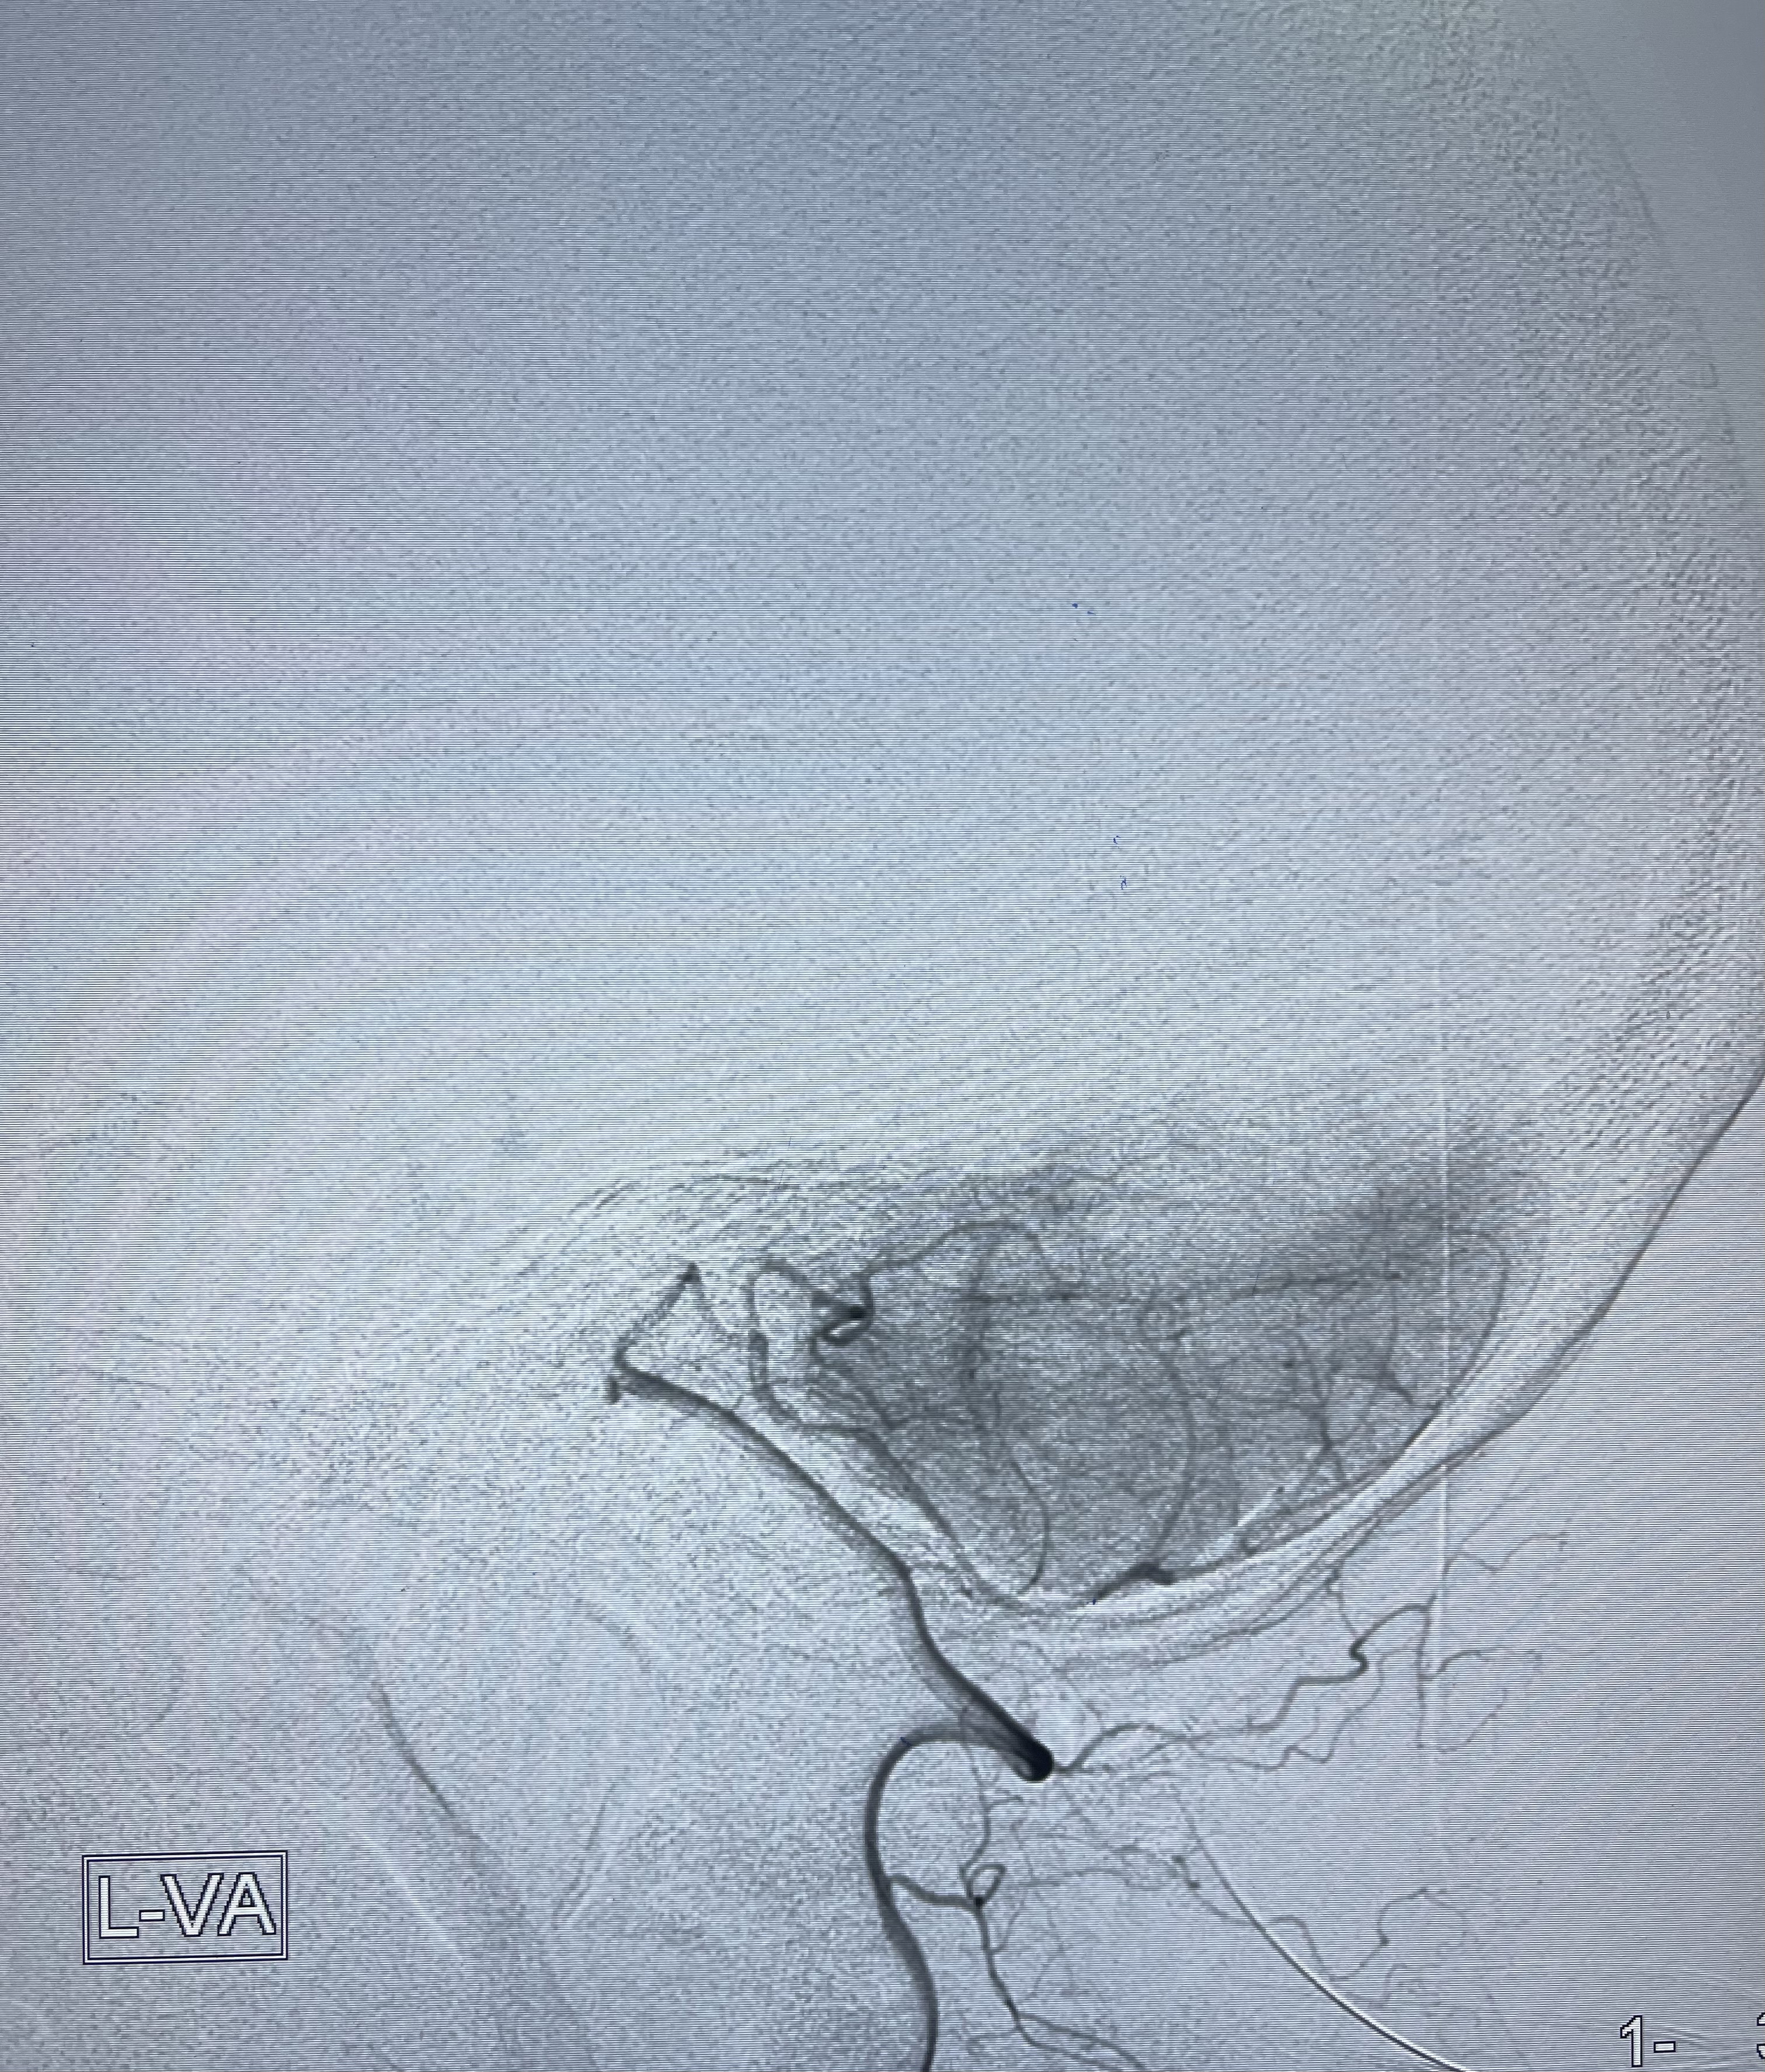

2021-01-11全麻下双微导管栓塞

工作角度显示瘤颈

E10 45°角微导管塑形后轻松到位

5-15cm三维圈成篮:瘤颈部覆盖弹簧圈

3-6cm

2-6

2-6cm

微弹簧圈尾端弹出动脉瘤,栓塞微导管轻轻送入动脉瘤内

1-4cm

1-2cm

动脉瘤致密填塞

麻醉苏醒佳